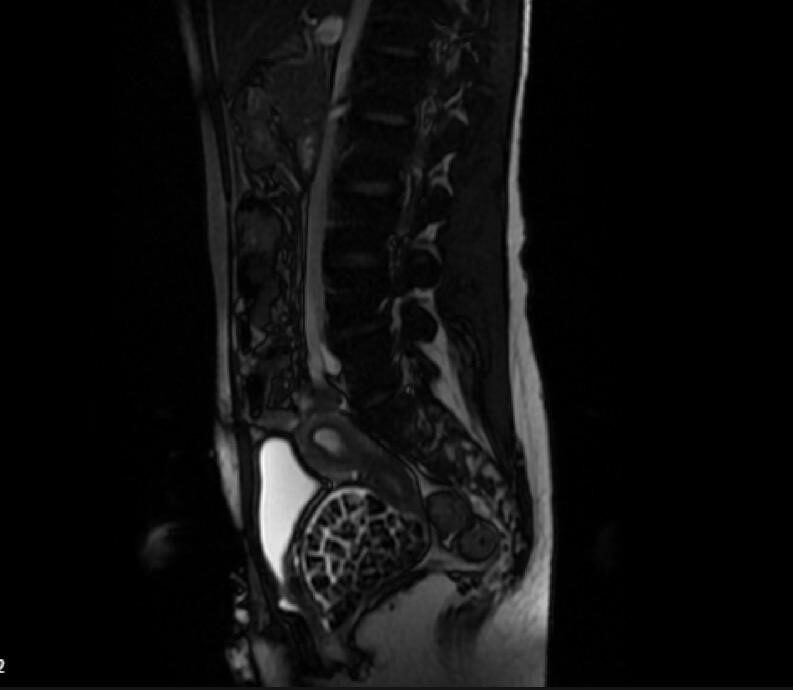

"Hastamızın 2004 yılında doğduğunu ardından doğar doğmaz ekstrofi vezika dediğimiz 50 binde bir görülen bir anomaliden dolayı art arda ameliyatlar geçirdiğini öğrendik. 10 yaşında yine bir ameliyat geçirmişti, gerekli görüntüleme ve tetkiklerimizi yaptırdık. Normalde mesanesinin olması gereken yerin hemen arka kısmında taşlarla dolu bir kese olduğunu gördük, bunun üzerine ek görüntülemeler; MR çektirdik.

Hastamız çelişkili açıklamalar almıştı, kendi radyolojik kliniğimiz ve edindiğimiz konsültasyonlarda taşların mesanede değil vajinal boşlukta oluştuğunu düşündük, bir planlama yaptık. Kadın doğum hocamızın da çabasıyla taşları tamamen temizledik ardından ileride normal bir hayat sürmesi bakımından oraya plastik cerrahi yaptık. 287 adet taş çıkardık, pratikte gerçekten görünce çok şaşırdık çünkü bu aynı zamanda literatürde çok nadir görülen bir olay.

"Mesane taşları olduğu düşünülerek daha büyük bir hastaneye refere edilmiş. Aramızda mini bir konsey yaparak muayene ettik. Vajen bir hazne görevi görerek orada durağan bir idrar, uzun süre beklediği için idrar içindeki minerallerde çökerek taşlar oluşmuş. Mesanedeki idrarın vajene akmış olabileceği ve vajende göllenen idrar nedeniyle taşların burada oluşacağını düşündük, ameliyatımızı planladık.

Ameliyata tanı amaçlı girmiştik, sistoskopi (Mesane gibi idrar yollarını kapsayan kısımlardaki rahatsızlıkların teşhis ve tedavisinde kullanılan endoskopik bir yöntem) dediğimiz ameliyatı Erkan Hocam ile birlikte gerçekleştirdik. Önce mesaneyi bir görüntüledik, mesane tabanına yaklaşık 2-3 cm’lik bir alandan vajene fistülize olduğunu gördük. Mesaneden vajene geçtiğimiz esnada tüm vajenin taşlarla dolu olduğunu gördük.

Tanı amacıyla girdiğimiz ameliyatta her şey de olağan gittiği için tedaviye geçtik. Taşların çıkabileceği kadar bir genişlik sağladık. Daha sonra yaklaşık en büyüğü 2,5 cm boyutlarında olan, irili ufaklı 287 tane taşı ameliyat esnasında çıkarmış olduk. Taşların tekrarlamaması için idrarın göllenmemesi, en azından dışarıya rahatça boşalabilmesi için vajinal rekonstrüksiyonu sağladık. Ameliyatta da herhangi bir problem yaşamadık. Literatürü Erkan Hocam ile birlikte değerlendirmiştik. Primer olarak vajende birikmiş olan bu kadar çok sayıda taşla ilgili bir makale görmedik, rastlamadık.